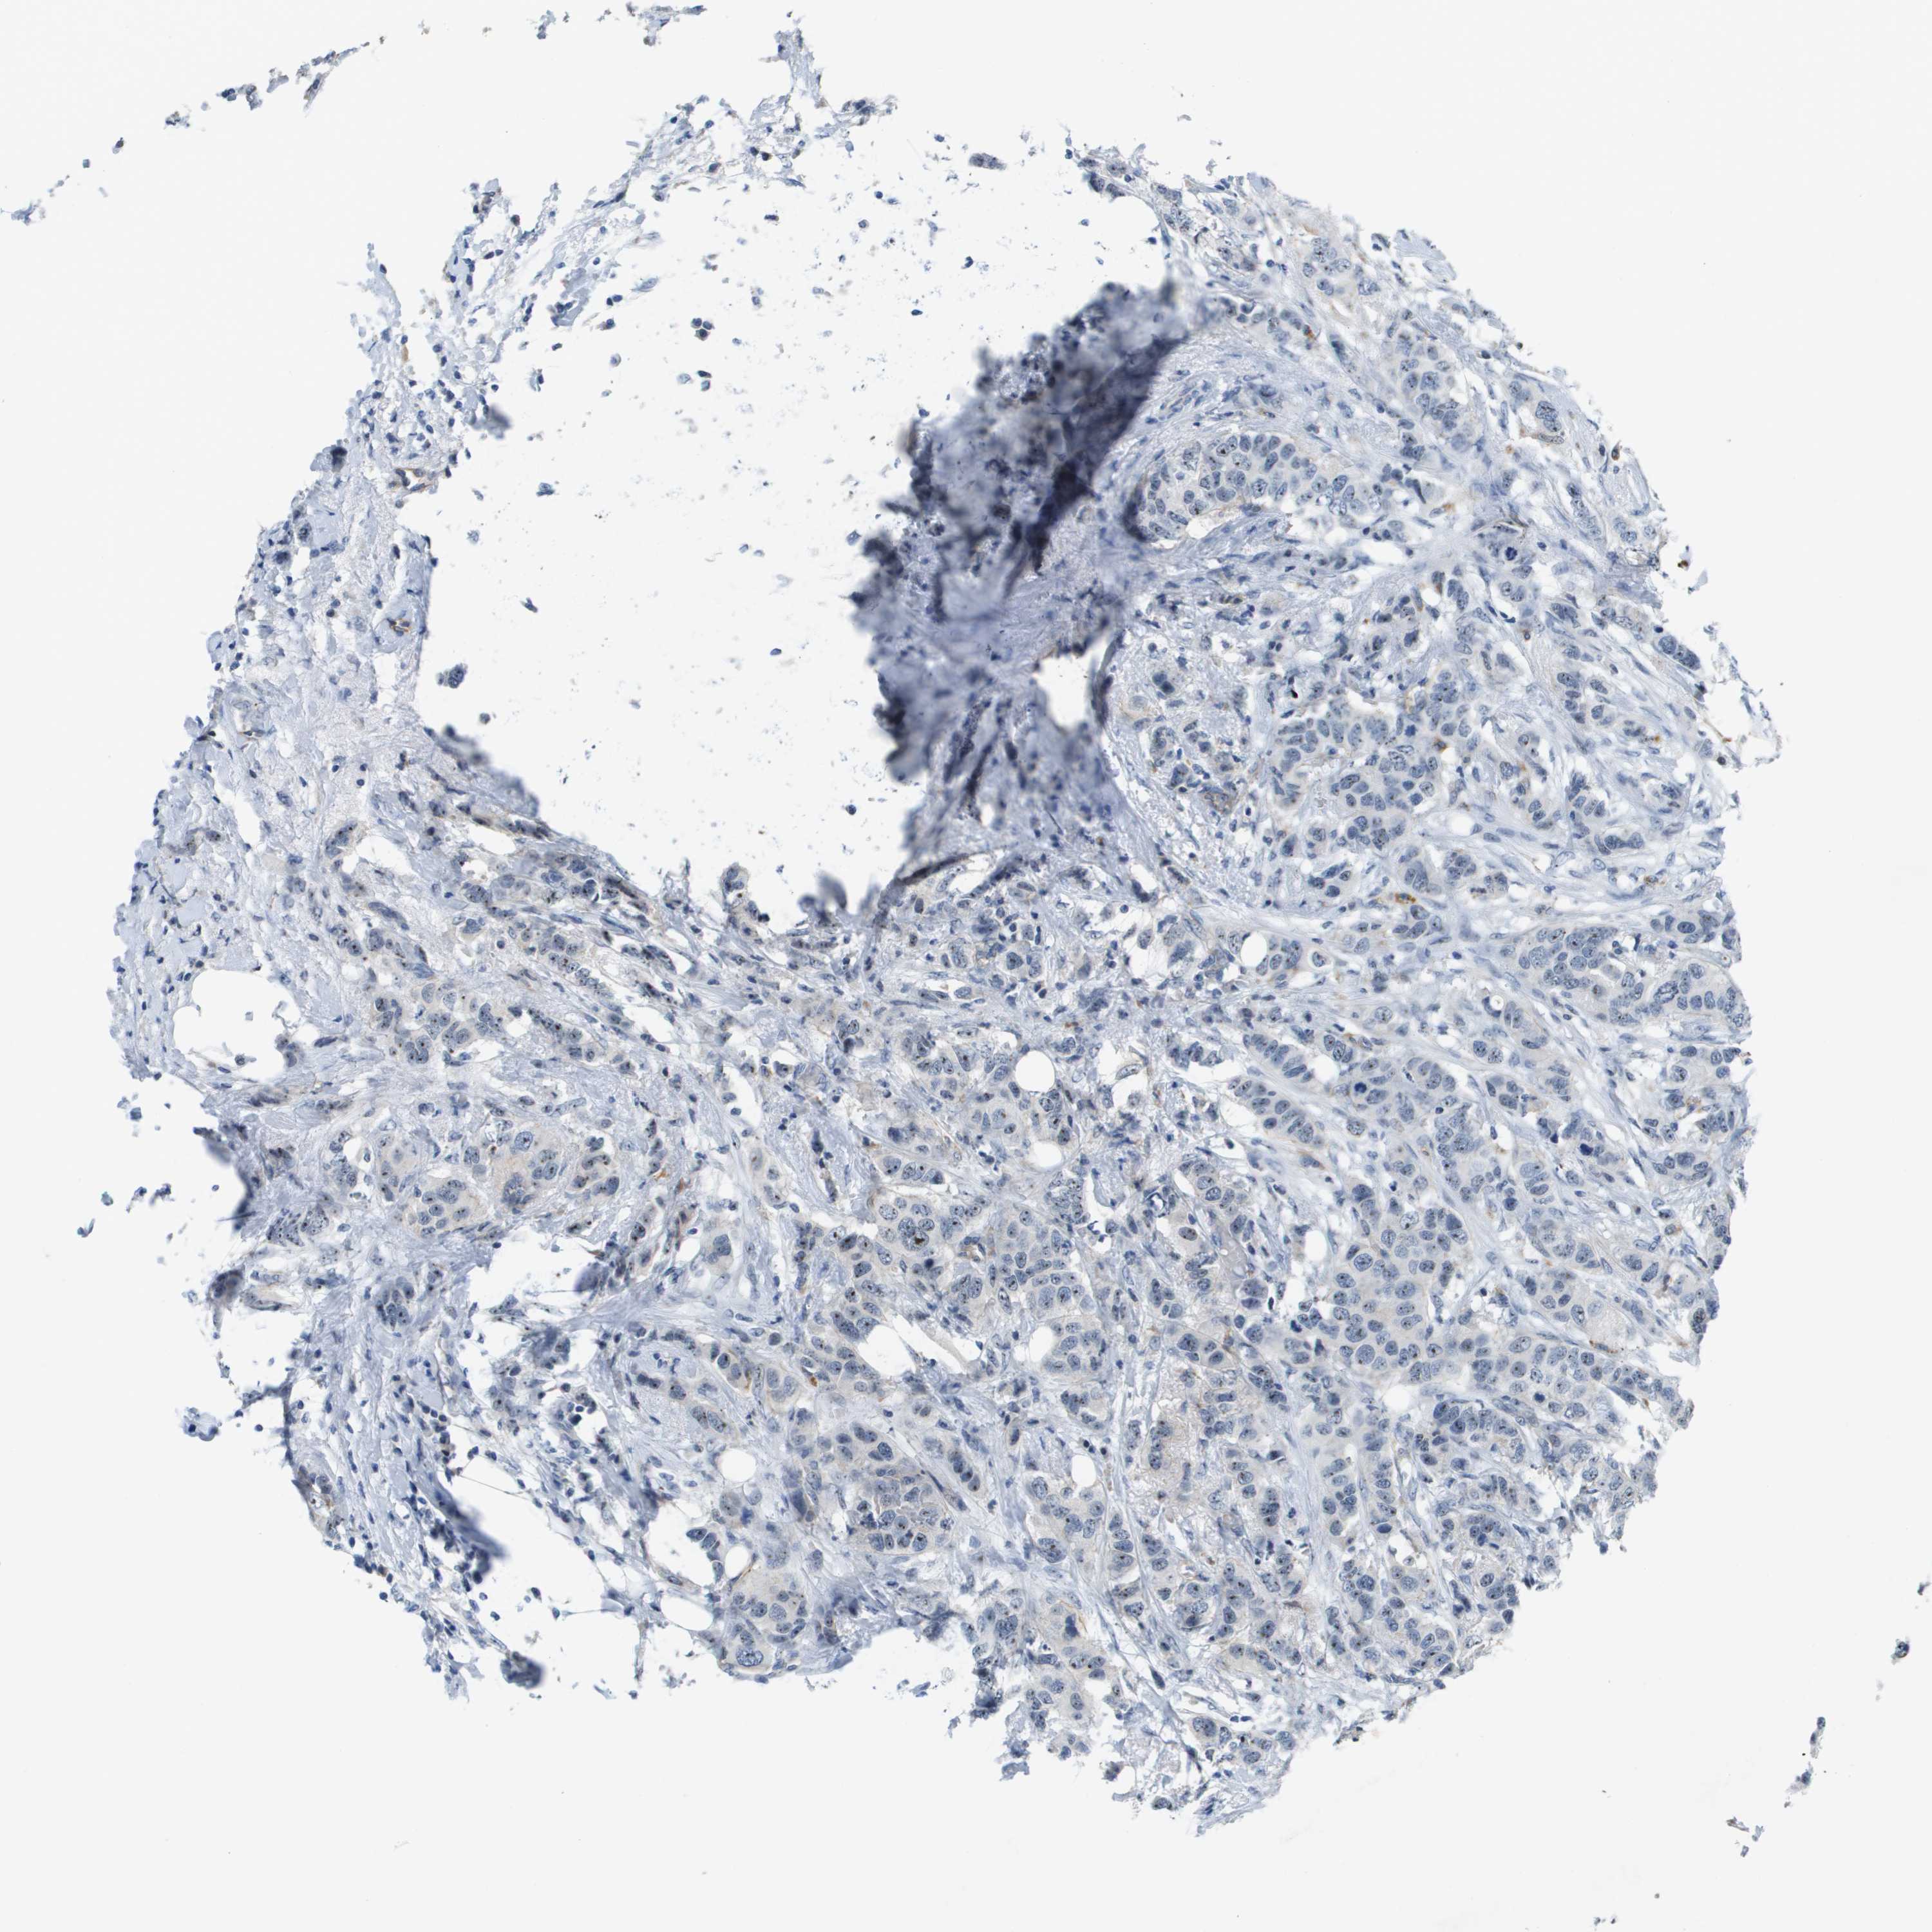

BRCA TCGA BRCA VALIDATION PROTEIN EXPRESSION